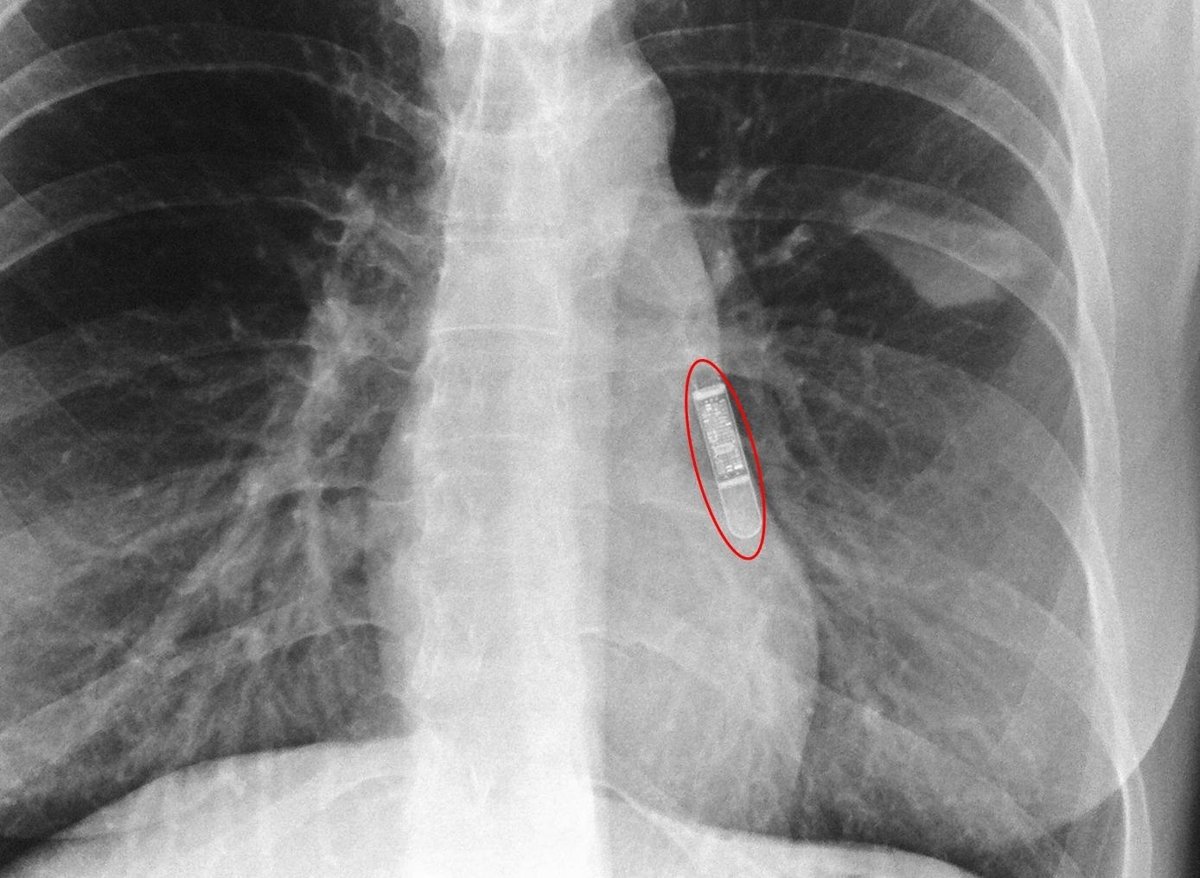

Imagen radiológica tras la implantación.

La novedad del dispositivo implantado por primera vez en el Complejo Hospitalario de Navarra es su reducido tamaño (más pequeño que el capuchón de un bolígrafo), lo que permite que su implantación pueda hacerse sin utilizar bisturí como hasta ahora, y, por tanto, sin puntos de sutura que deban ser retirados con posterioridad. Así, el Holter se implanta a través de una mínima incisión de tan sólo unos pocos milímetros mediante la inyección del aparato debajo de la piel.

La principal ventaja que presenta este nuevo dispositivo es la comodidad para el paciente ya que, gracias a su mínimo tamaño, no se nota ningún 'bulto' bajo la piel. Otra ventaja es que debido a su tecnología avanzada que incorpora transmisión de datos inalámbrica, el seguimiento puede realizarse íntegramente desde el domicilio del paciente de forma automática, todo ello gracias a un monitor que se entrega al paciente y que recoge la información recopilada por el dispositivo, transmitiéndola por telefonía móvil al hospital.